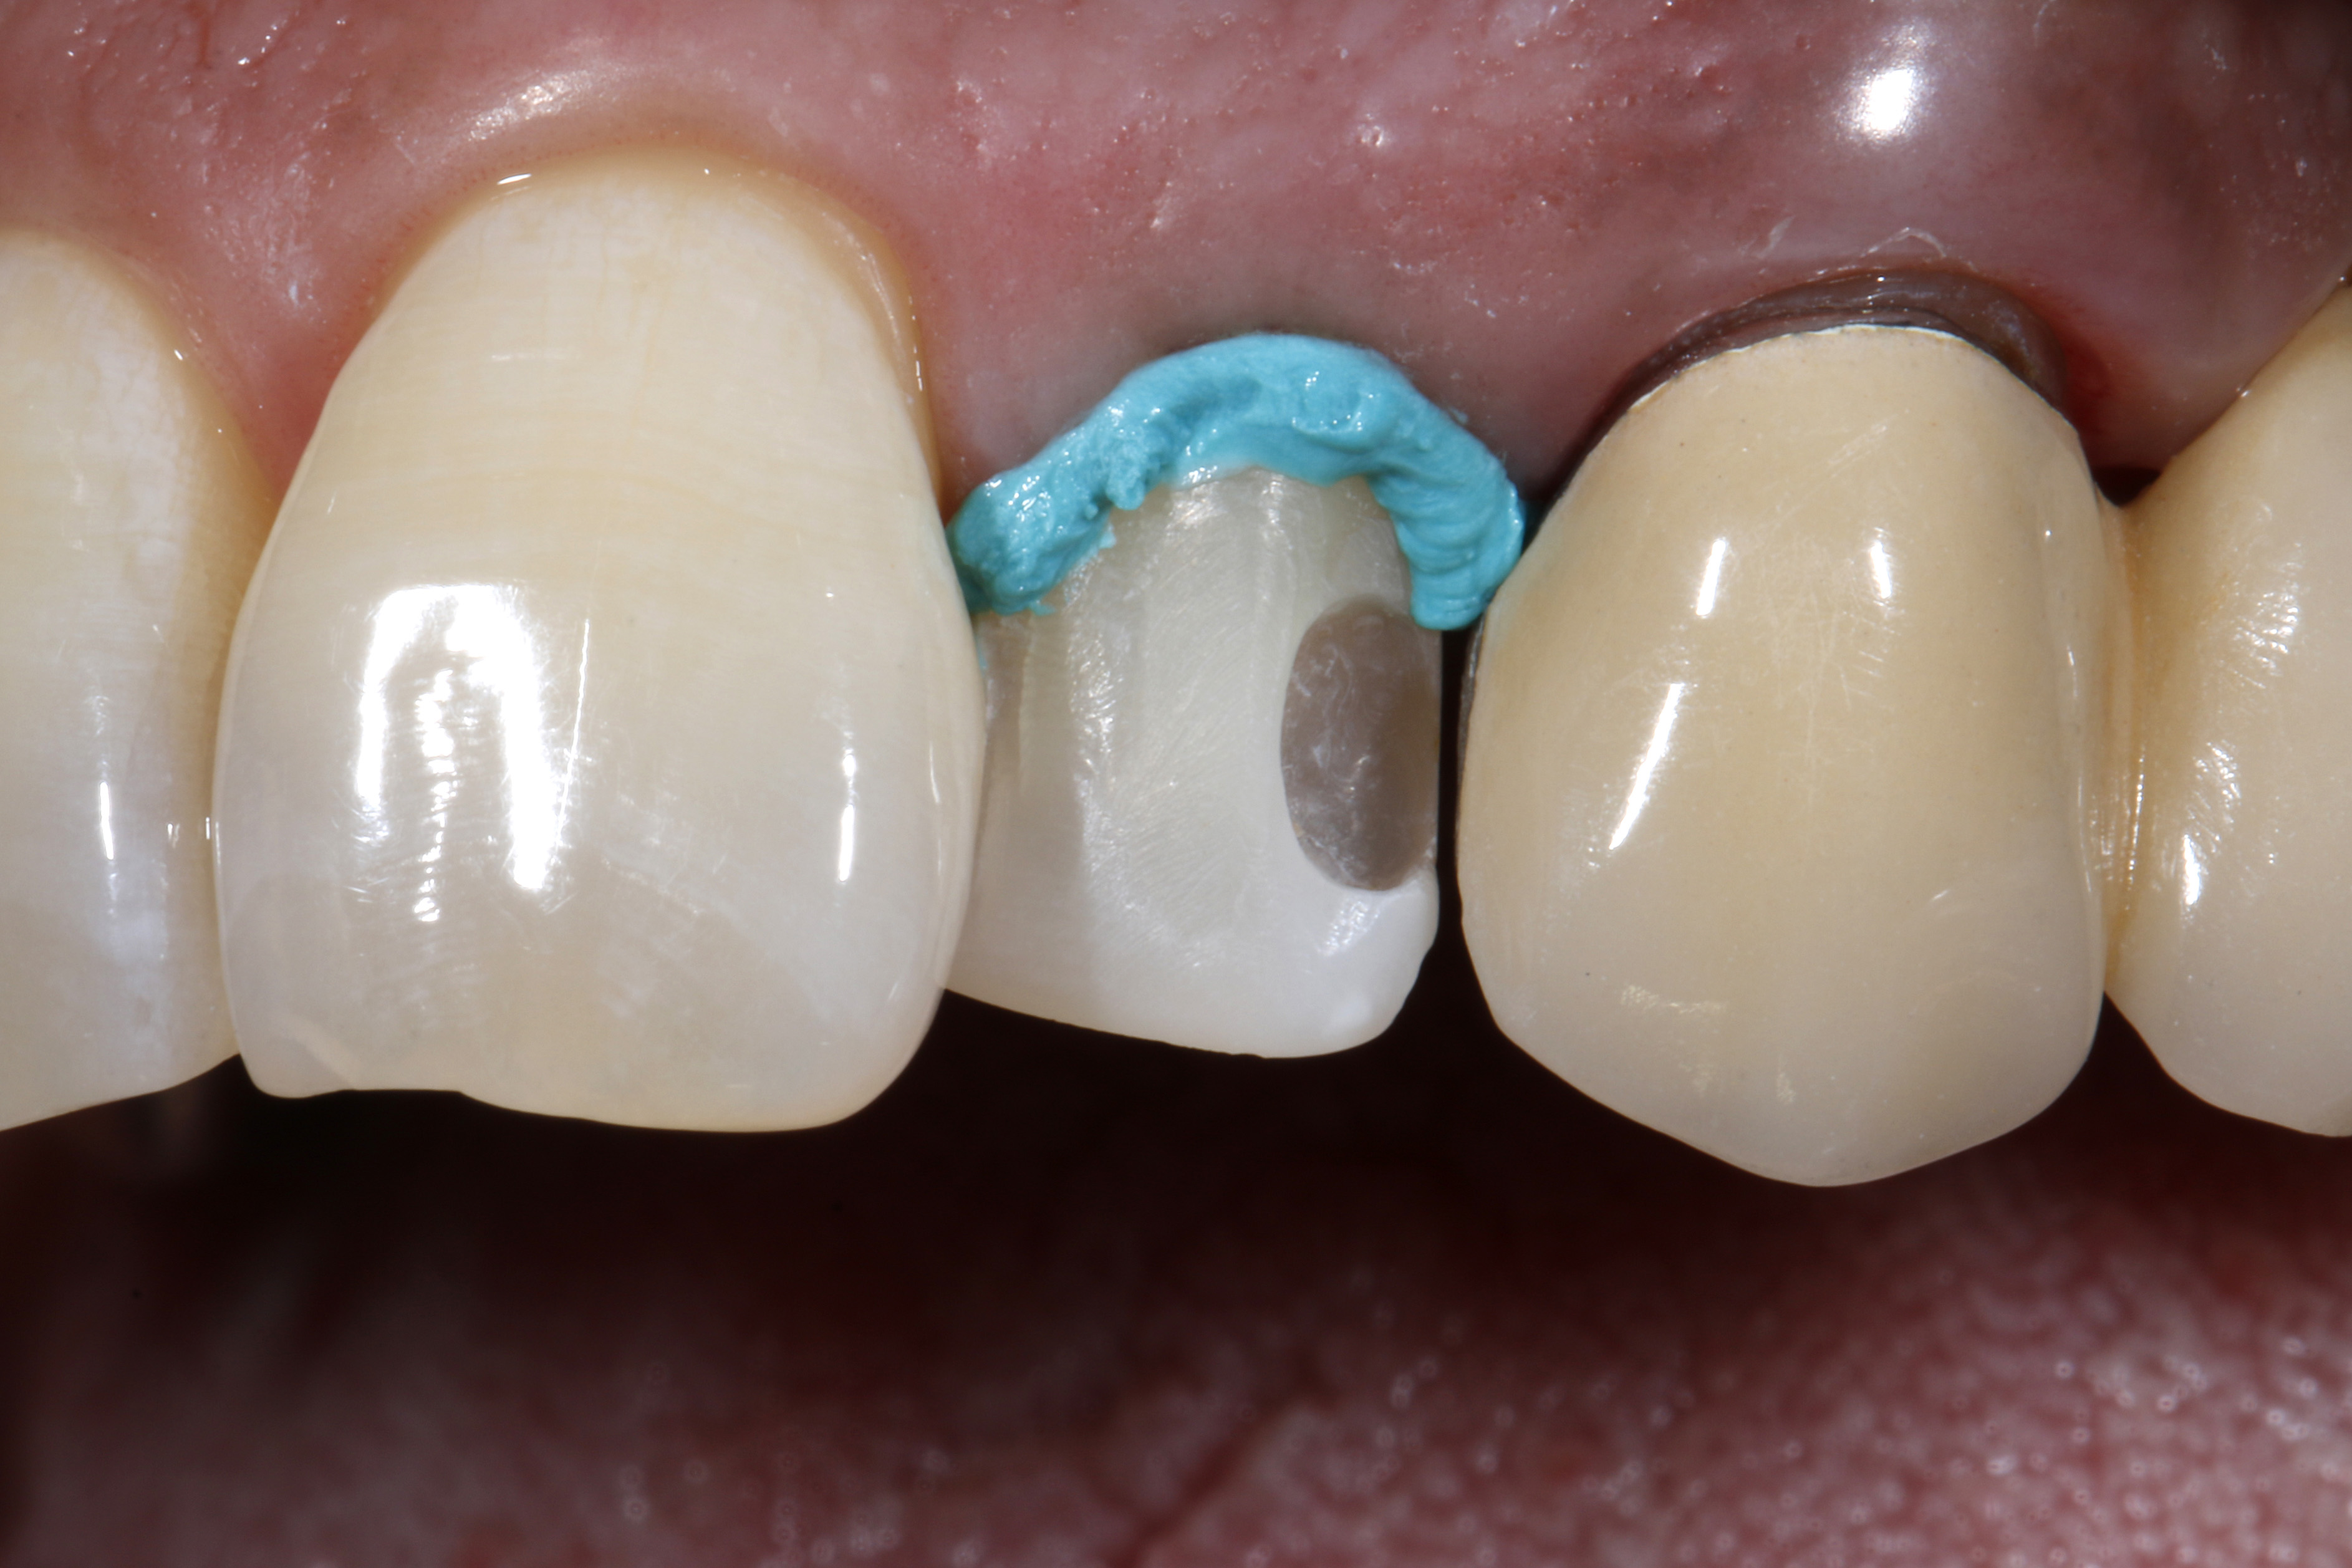

Leczenie rozpoczęto od dokładnego oczyszczenia zęba z zewnętrznych osadów za pomocą pasty profilaktycznej bez fluoru i gumki w kształcie kielicha. Następnie odpowiedni odcień kompozytu określono na wciąż wilgotnym zębie (ryc. 3).

Ryc. 3. Dobór odcienia na wilgotnym zębie

Wybrany odcień kompozytu sprawdzono, nakładając niewielką porcję kompozytu na powierzchnię zęba, który nie został wysuszony i nie był wstępnie zabezpieczony materiałem wiążącym (17). Konieczna jest polimeryzacja próbki kompozytu światłem przez czas określony przez producenta w celu uzyskania miarodajnego porównania optycznego. Dopiero przy wystarczającej ekspozycji na światło fotoinicjator kamforochinon, który jest zawarty w większości kompozytów i ma intensywnie żółty kolor, ulega w dużej mierze zużyciu i przekształceniu w bezbarwny produkt reakcji („fotowybielacz”) (18–23). Po polimeryzacji próbki kompozytu nałożonej na powierzchnię zęba, jej właściwości optyczne porównano z otaczającą zęba substancją pod względem odcienia i stopnia przezierności. Na tym etapie można łatwo dokonać korekty, zastępując niedopasowaną optycznie próbkę materiałem kompozytowym o zoptymalizowanym odcieniu. Ten indywidualny proces weryfikacji, który zajmuje bardzo mało czasu, gwarantuje, że do kolejnej odbudowy zostanie użyty optymalnie dopasowany materiał kompozytowy. Oznacza to, że w niemal wszystkich przypadkach można uniknąć czasochłonnych poprawek, a nawet nowych wypełnień z powodu skarg pacjentów na estetykę.

Ryc. 4. Usunięcie starego, dystalnego wypełnienia kompozytowego i niewielka preparacja powierzchni wargowej pod bezpośrednią licówkę kompozytową.